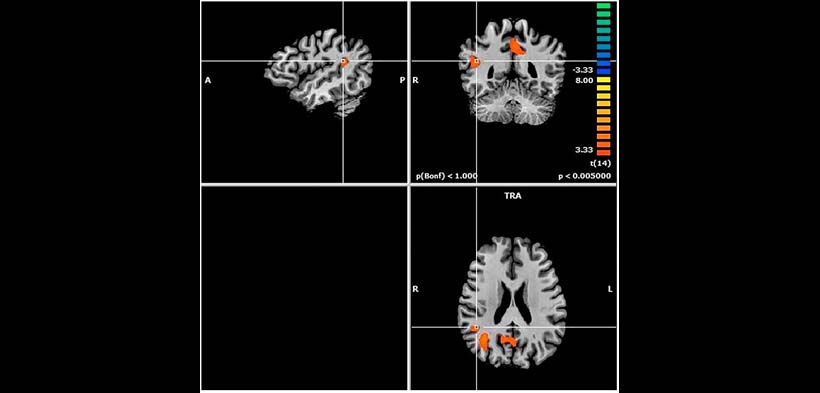

Fig. 2. RMF de un paciente sano. Se observa menor actividad cerebral, se muestra también tres grupos de aumentos en la oxigenación de la sangre. A, anterior; COR, coronal; L, izquierda; P, posterior; R, a la derecha; SAG, sagital; TRA, transversal.